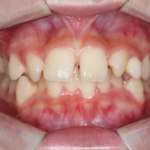

【叢生】インビザライン症例:ガタガタが気になる

治療前 治療後 症例の詳細 主訴 ガタガタが気になる ...